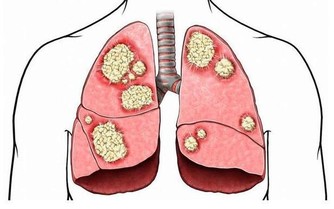

近年來,胰腺癌的發病人數也不容小覷,而且大約有一半的新增患者年齡都在60歲以上。胰腺癌非常難被治愈,5年生存率小於1%,所以在醫學上被稱為“癌症之王”。

胰腺癌的常見症狀包括背痛、胃痛、體重異常減輕等,最為明顯的跡像是皮膚和眼白開始泛黃。另外,一個不容忽視的事實是,有超過30%的胰腺癌患者在確診患上這種惡性腫瘤前,被診斷出2型糖尿病。醫生認為,這可能是胰腺腫瘤干擾了胰島素分泌的結果,才會導致出現糖尿病。